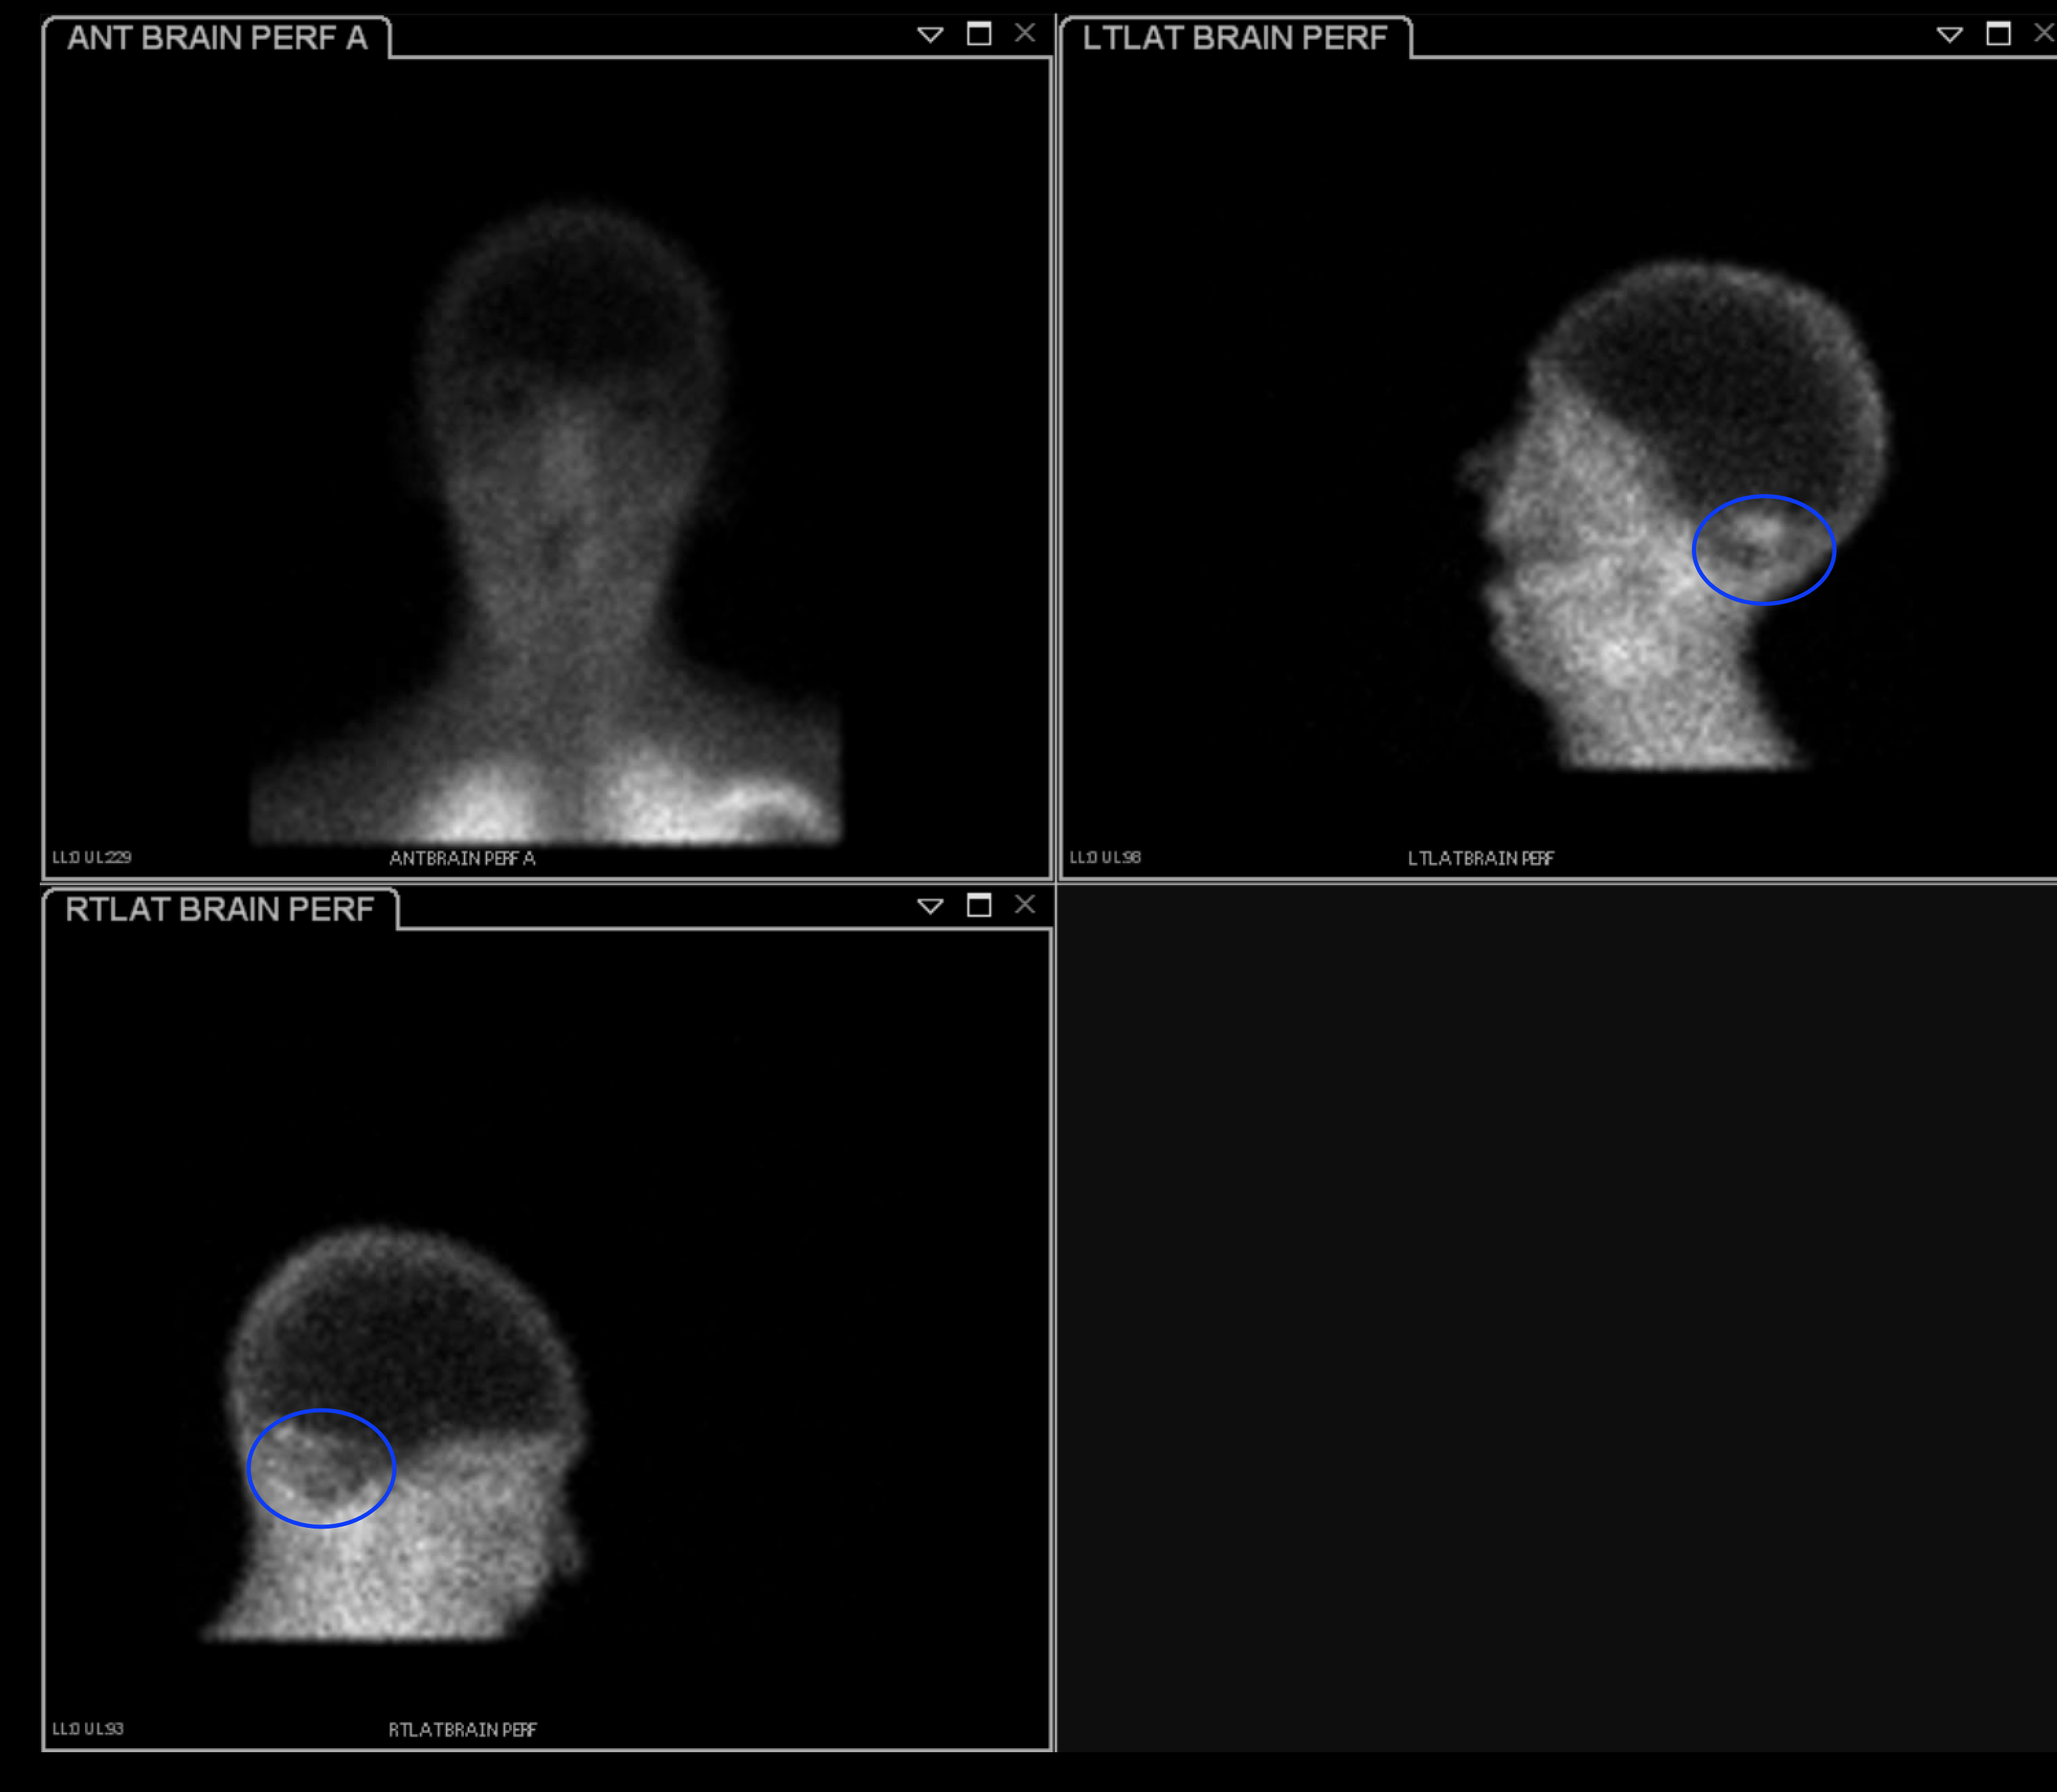

Age: 32

Sex: Male

Indication: Nontraumatic intracranial hemorrhage with cardiac arrest

Radiotracer: Tc99m ECD

Sample ReportAlthough no cerebral perfusion is present, there is an area of cerebellar perfusion, which is not consistent with brain death. This exam may be repeated in 24 hours if clinically indicated.